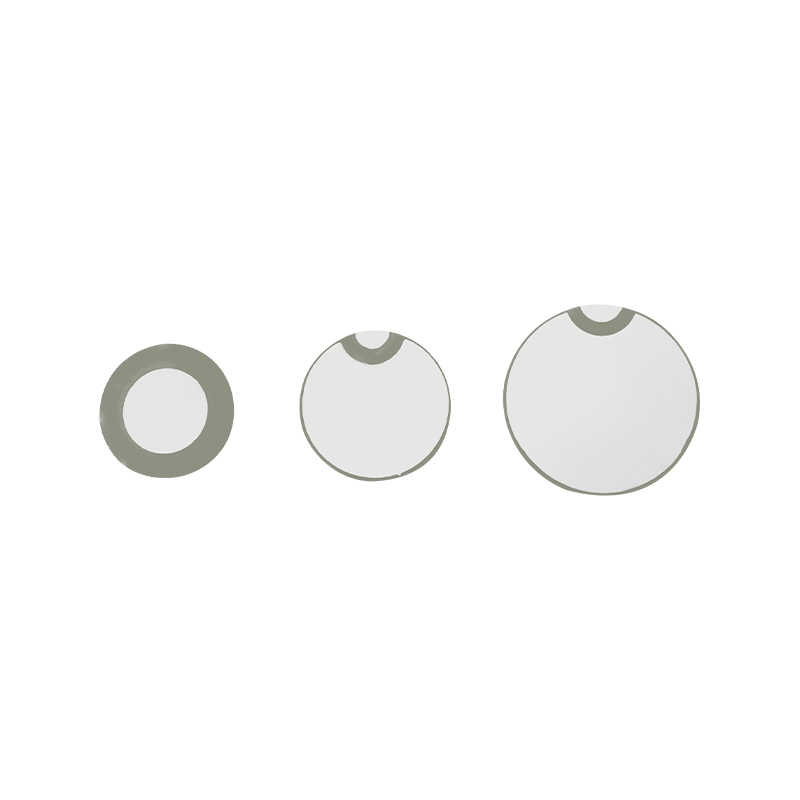

Lékařské síťové nebulizační tablety jsou přesné součásti používané v lékařských zařízeních k přeměně léků nebo roztoků na malé aerosolové částice pro léčbu různých respiračních poruch, jako je astma a chronická obstrukční plicní nemoc (CHOPN) atd. inhalací. Konstrukce a výběr materiálu vrstvy nebulizátoru je rozhodující pro zajištění účinného podávání léčiva a pohodlí pacienta. Nerezový membránový plech je v ocelovém plechu proražen tisíci malých 2-3μm síťových otvorů v ocelovém plechu pomocí technologie laserového vrtání v přesném laserovém procesu a poté je pevně spojen s piezoelektrickým keramickým kruhovým plechem, který převádí rezonanční frekvenci piezoelektrického plechu na vysokofrekvenční vibrační energii prostřednictvím výstupního signálu desky ovladače PCB a rychle rozbíjí kapalinu. léky na jemné aerosolové částice. Tyto kapičky se také nazývají střední velikost částic, když střední procento velikosti částic D50 dosáhne > 60 % nebo více, částice budou dostatečně malé, aby se mohly dýcháním dostat hluboko do plic k povrchu alveol, čímž se zlepší absorpční účinnost léku a terapeutický účinek. Micro mesh nebulizérový list Medical Mesh má hlavně několik forem, nerezový mikrosíťový nebulizační list, nikl-palladium lékařský nebulizační list, PI polymerový lékařský nebulizační list a tak dále. Všechny výše uvedené jsou prostřednictvím piezoelektrické keramické vibrační přeměny energie k dosažení atomizačního efektu.

Polyimid (Polyimid) označovaný jako PI, je nejlepší komplexní výkon organických polymerních materiálů, má vynikající chemickou stabilitu a může odolat korozi různých léků, aby bylo zajištěno dlouhodobé používání atomizovaných tablet. Kromě toho je vynikající tepelná stabilita polymerního PI filmu, s dlouhodobým používáním teplotního rozsahu -200 ~ 300 ° C, vysokou izolací, ochranou životního prostředí a netoxicitou, jako speciální inženýrský materiál, široce používaný v letecké mikroelektronice, separační membrány z nano-kapalných krystalů a další obory, byl v 21. století zahrnut zeměmi jednoho z nejslibnějších inženýrských materiálů. deformované v procesu vysokoteplotní dezinfekce, aby bylo zajištěno opětovné použití! Pro sex a bezpečnost používáme laserovou technologii pro laserovou perforaci, PI film implantovaný mezi nerezovou ocel a piezoelektrickou fólii, použití piezoelektrické keramické ultrazvukové technologie tak, aby se atomizované kapičky přes PI film rozptýlily do atomizace 3 ~ 4 μm částic pro inhalaci lékařskou nebulizací, bezpečnost většiny uživatelů miluje, vyrobeno z hlavního nebulizéru s PI výhoda non-ucpání, vnitřní stěna otvoru v hladké a zaoblené, žádné zbytky kapaliny, atomizace jemné a stabilní. Atomizace je jemná a stabilní. Tablety PI filmového nebulizátoru mohou účinně zabránit zbytkům léků, snížit riziko křížové kontaminace. V praktické aplikaci se také promítly charakteristiky nízké spotřeby energie polymerních PI membránových nebulizačních tablet, shrnuto, polymerové PI membránové nebulizační tablety se se svým vynikajícím výkonem a konstrukčními výhodami staly nepostradatelnou součástí oblasti lékařské nebulizační terapie.